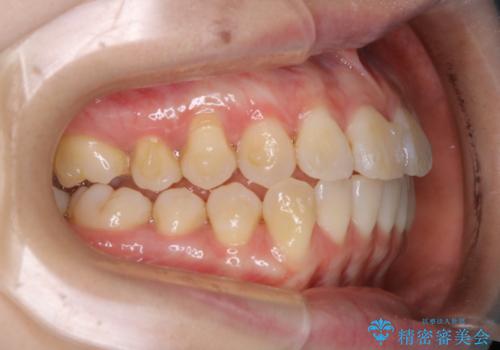

- 前歯のがたつきが気になるとご相談にいらした方です。右側前歯部のクロスバイトの他、左側にもシザーズバイトが認められたため、インビザラインにて治療を行いました。出産直後のため、ご自身の時間がなかなか取れないとの事で、最小限の来院回数で治療を勧められるように計画しました。

患者様ご自身で使用時間をしっかり管理して頂くことを条件に、最低限の来院回数で治療を進めていきました。20時間以上の使用を厳守して頂けたことで、少ない来院回数にて治療を終了することが出来ました。前よりも噛みやすくなったと大変喜んでいただけました。